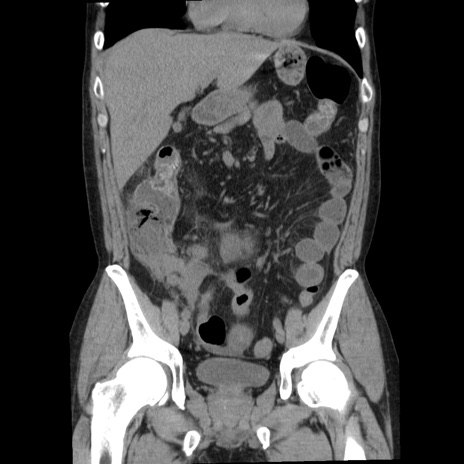

横断像

【症例】40歳代男性

【現病歴】2日前から胃痛あり。徐々に周期的な激痛に変化した。本日になっても激痛があるため受診。

【身体所見】意識清明、BT 38-39℃台あり、腹部:膨満、やや硬、右下腹部に圧痛あり。

【データ】WBC 8500、CRP 23.26